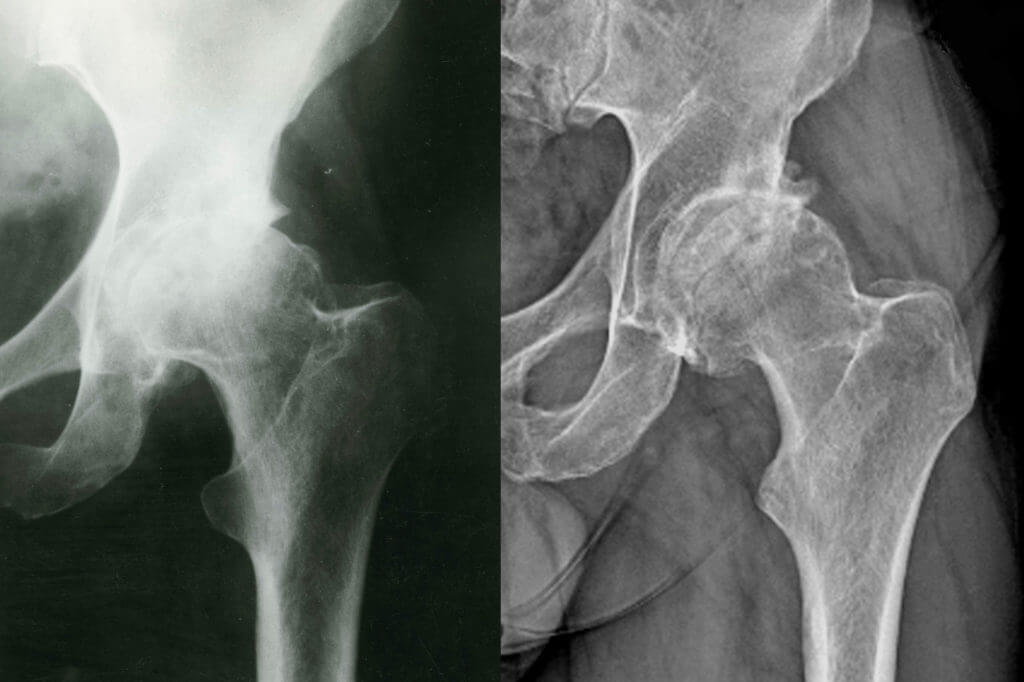

Imaging tests are typically needed to confirm the diagnosis and evaluate the severity of the condition:

- X-rays: X-rays can reveal changes in the bone structure of the femoral head, particularly in the later stages when the bone begins to collapse.

- MRI: An MRI is the most sensitive test for diagnosing AVN in its early stages, as it can detect changes in the bone before they are visible on X-rays.